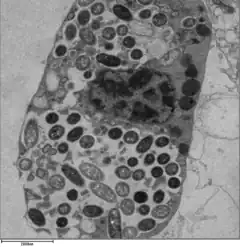

L. pneumophila is able to invade and replicate within human alveolar macrophages. Internalization of the bacteria appears to occur through phagocytosis or coiling phagocytosis and is reliant on Dot/Icm type 4B secretion system (T4BSS). Once internalized, the Dot/Icm system begins secreting bacterial effector proteins that recruit host factors to the Legionella containing vacuole (LCV). This process prevents the LCV from fusing with the lysosomes that would otherwise degrade the bacteria. Vesicles of the host cell's rough endoplasmic reticulum are attracted to the LCV, and these vacuoles supply the LCV with necessary lipids and proteins.[13] LCV membrane integrity requires a steady supply of host lipids, such as cellular cholesterol and the cis-monounsaturated fatty acid, palmitoleic acid.[31][32] L. pneumophila replication occurs within the LCV. Once nutrients are depleted, the bacteria gain flagella and cytoxicity. To exit the host cell, L. pneumophila lyses the LCV and resides in the cytoplasm. In the cytoplasm, L. pneumophila inhibit organelle and plasma membrane function and structure which ultimately leads to osmotic lysis of the host cell.[33]

Legionella-containing vacuole

For Legionella to survive within macrophages and protozoa, it must create a specialized compartment known as the Legionella-containing vacuole (LCV).[37] Through the action of the Dot/Icm secretion system, the bacteria are able to prevent degradation by the normal endosomal trafficking pathway and instead replicate. Shortly after internalization, the bacteria specifically recruit endoplasmic reticulum-derived vesicles and mitochondria to the LCV while preventing the recruitment of endosomal markers such as Rab5a and Rab7a. Formation and maintenance of the vacuoles are crucial for pathogenesis; bacteria lacking the Dot/Icm secretion system are not pathogenic and cannot replicate within cells, while deletion of the Dot/Icm effector SdhA results in destabilization of the vacuolar membrane and no bacterial replication.[38][39]